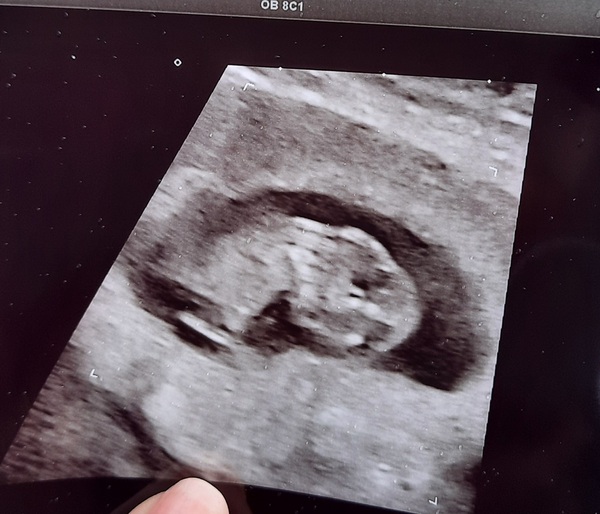

I had another scan at the Recurrent Miscarriage Clinic today and very happy to report my rainbow baby Purple still doing very well, measuring good and strong heartbeat 💜🌈 A huge relief for now xx